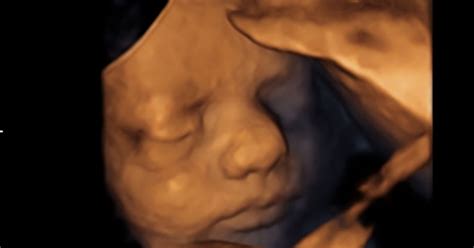

- Ultrazvočni pregled morfologije ploda: Opravi se med 19. in 23. tednom nosečnosti. Pri tem pregledu ugotavljajo ustreznost plodovega razvoja, morebitne nepravilnosti v razvoju ploda, ustreznost plodove rasti, količino plodovnice ter strukturo in lego posteljice.